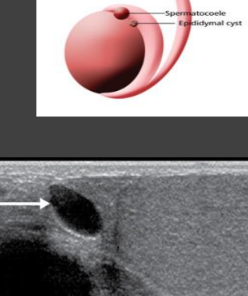

epididymal cysts

small clear cysts with serous fluid that are asymptomatic but may be palpable

spermatocele

cystic dilation of the efferent ductules of epi and always in epi head

__________________ are seen more often following a vasectomy

spermatoceles